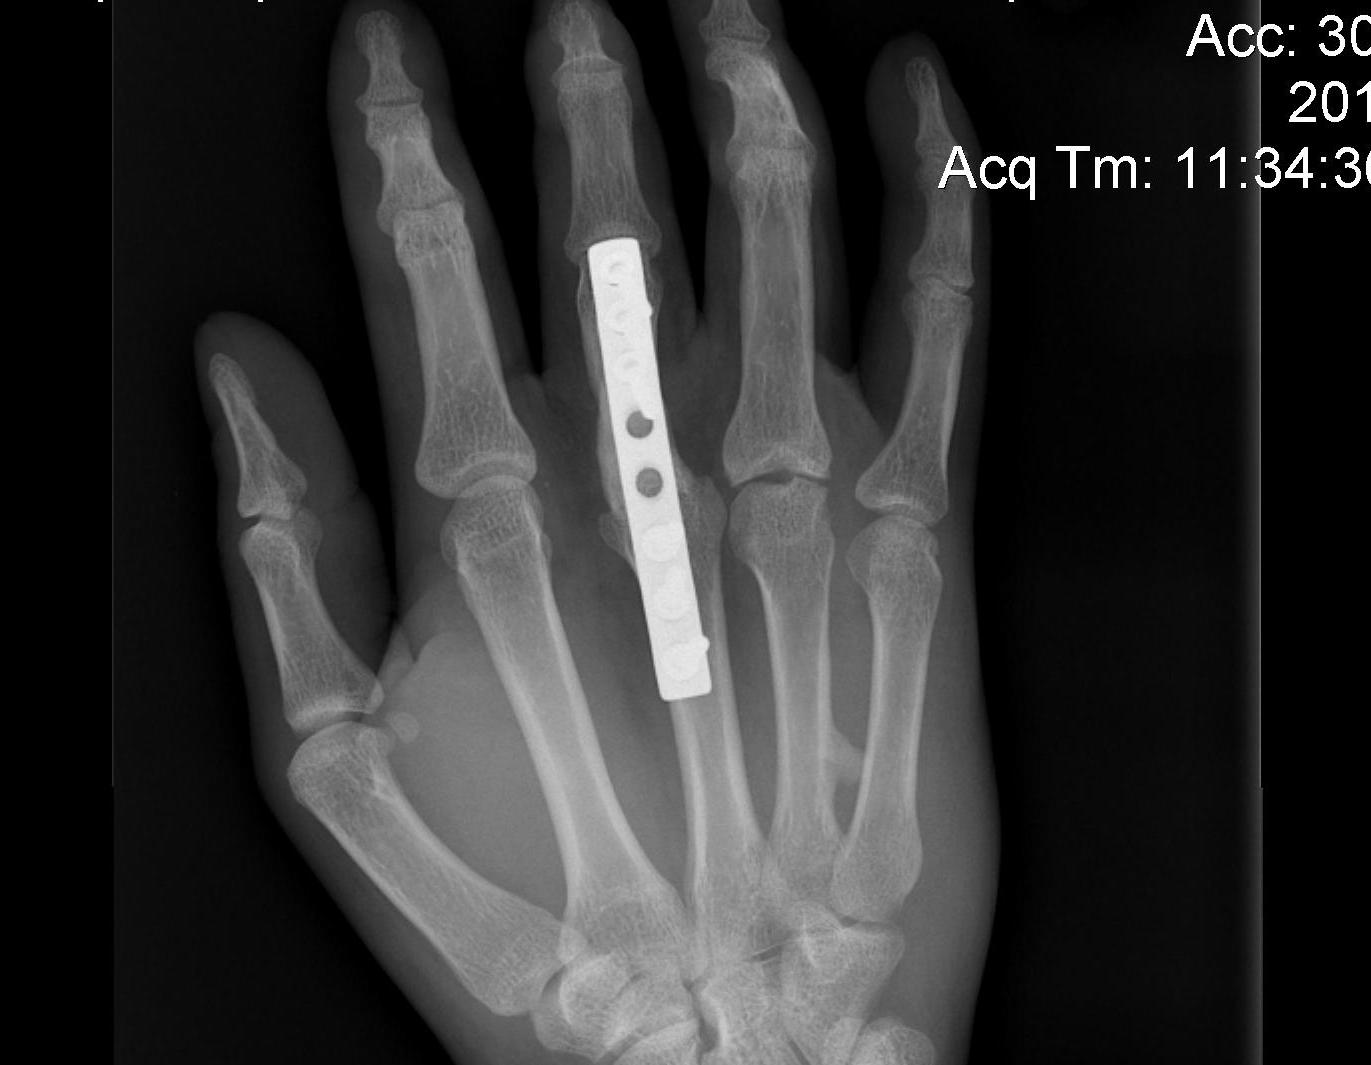

ORIF

A. Transverse fractures

- cross K wire

- Lister’s intra-osseous wire fixation

- plating

B. Long oblique / spiral fractures

Options

- percutaneous K wires / screw fixation / plating